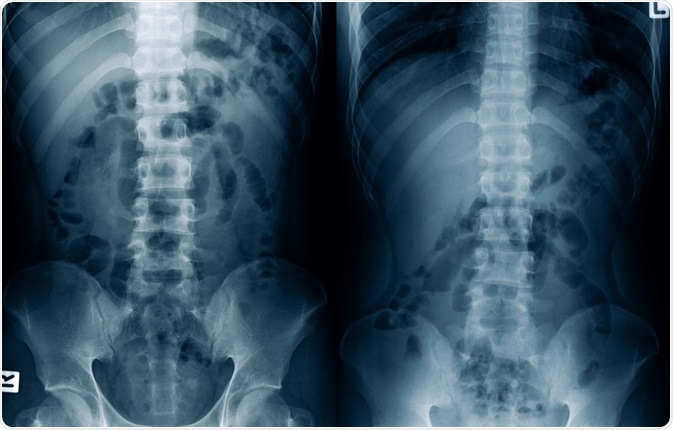

Ileus is a term used to describe the functional and non-mechanical inhibition of propulsive bowel activity, regardless of the pathologic mechanism. Ileus should be differentiated from a mechanical bowel obstruction, which is when GI motility is inhibited due to different structural abnormalities like tumors, hernias, intestinal adhesions, and twisting of the intestine.

Image Credit: MossStudio / Shutterstock.com

A distinction between postoperative ileus and mechanical small-bowel obstruction is sometimes difficult and confusing. A useful tool for distinguishing these two entities is computerized tomography (CT), although even plain radiography can help establish a correct diagnosis in certain cases.